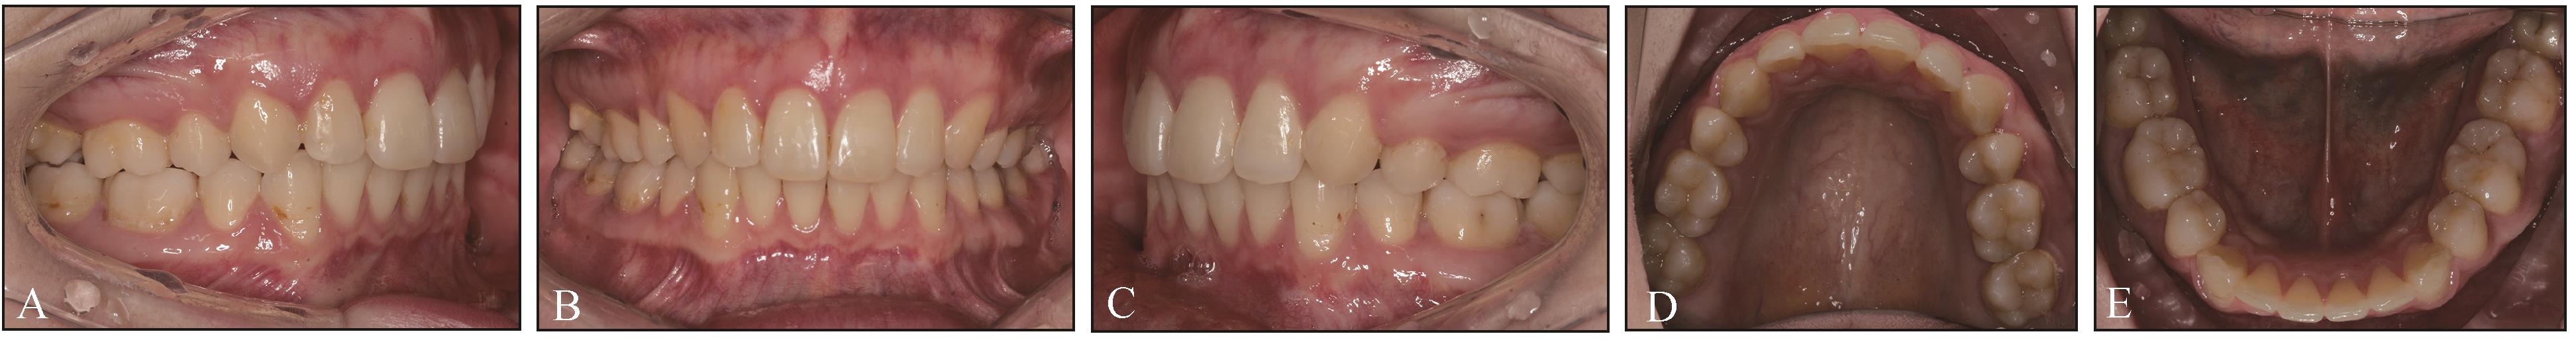

图 10

病例1保持1年后面颌像A~C:患者口内右侧、正面和左侧咬合照;D、E:患者上颌、下颌口内照。"